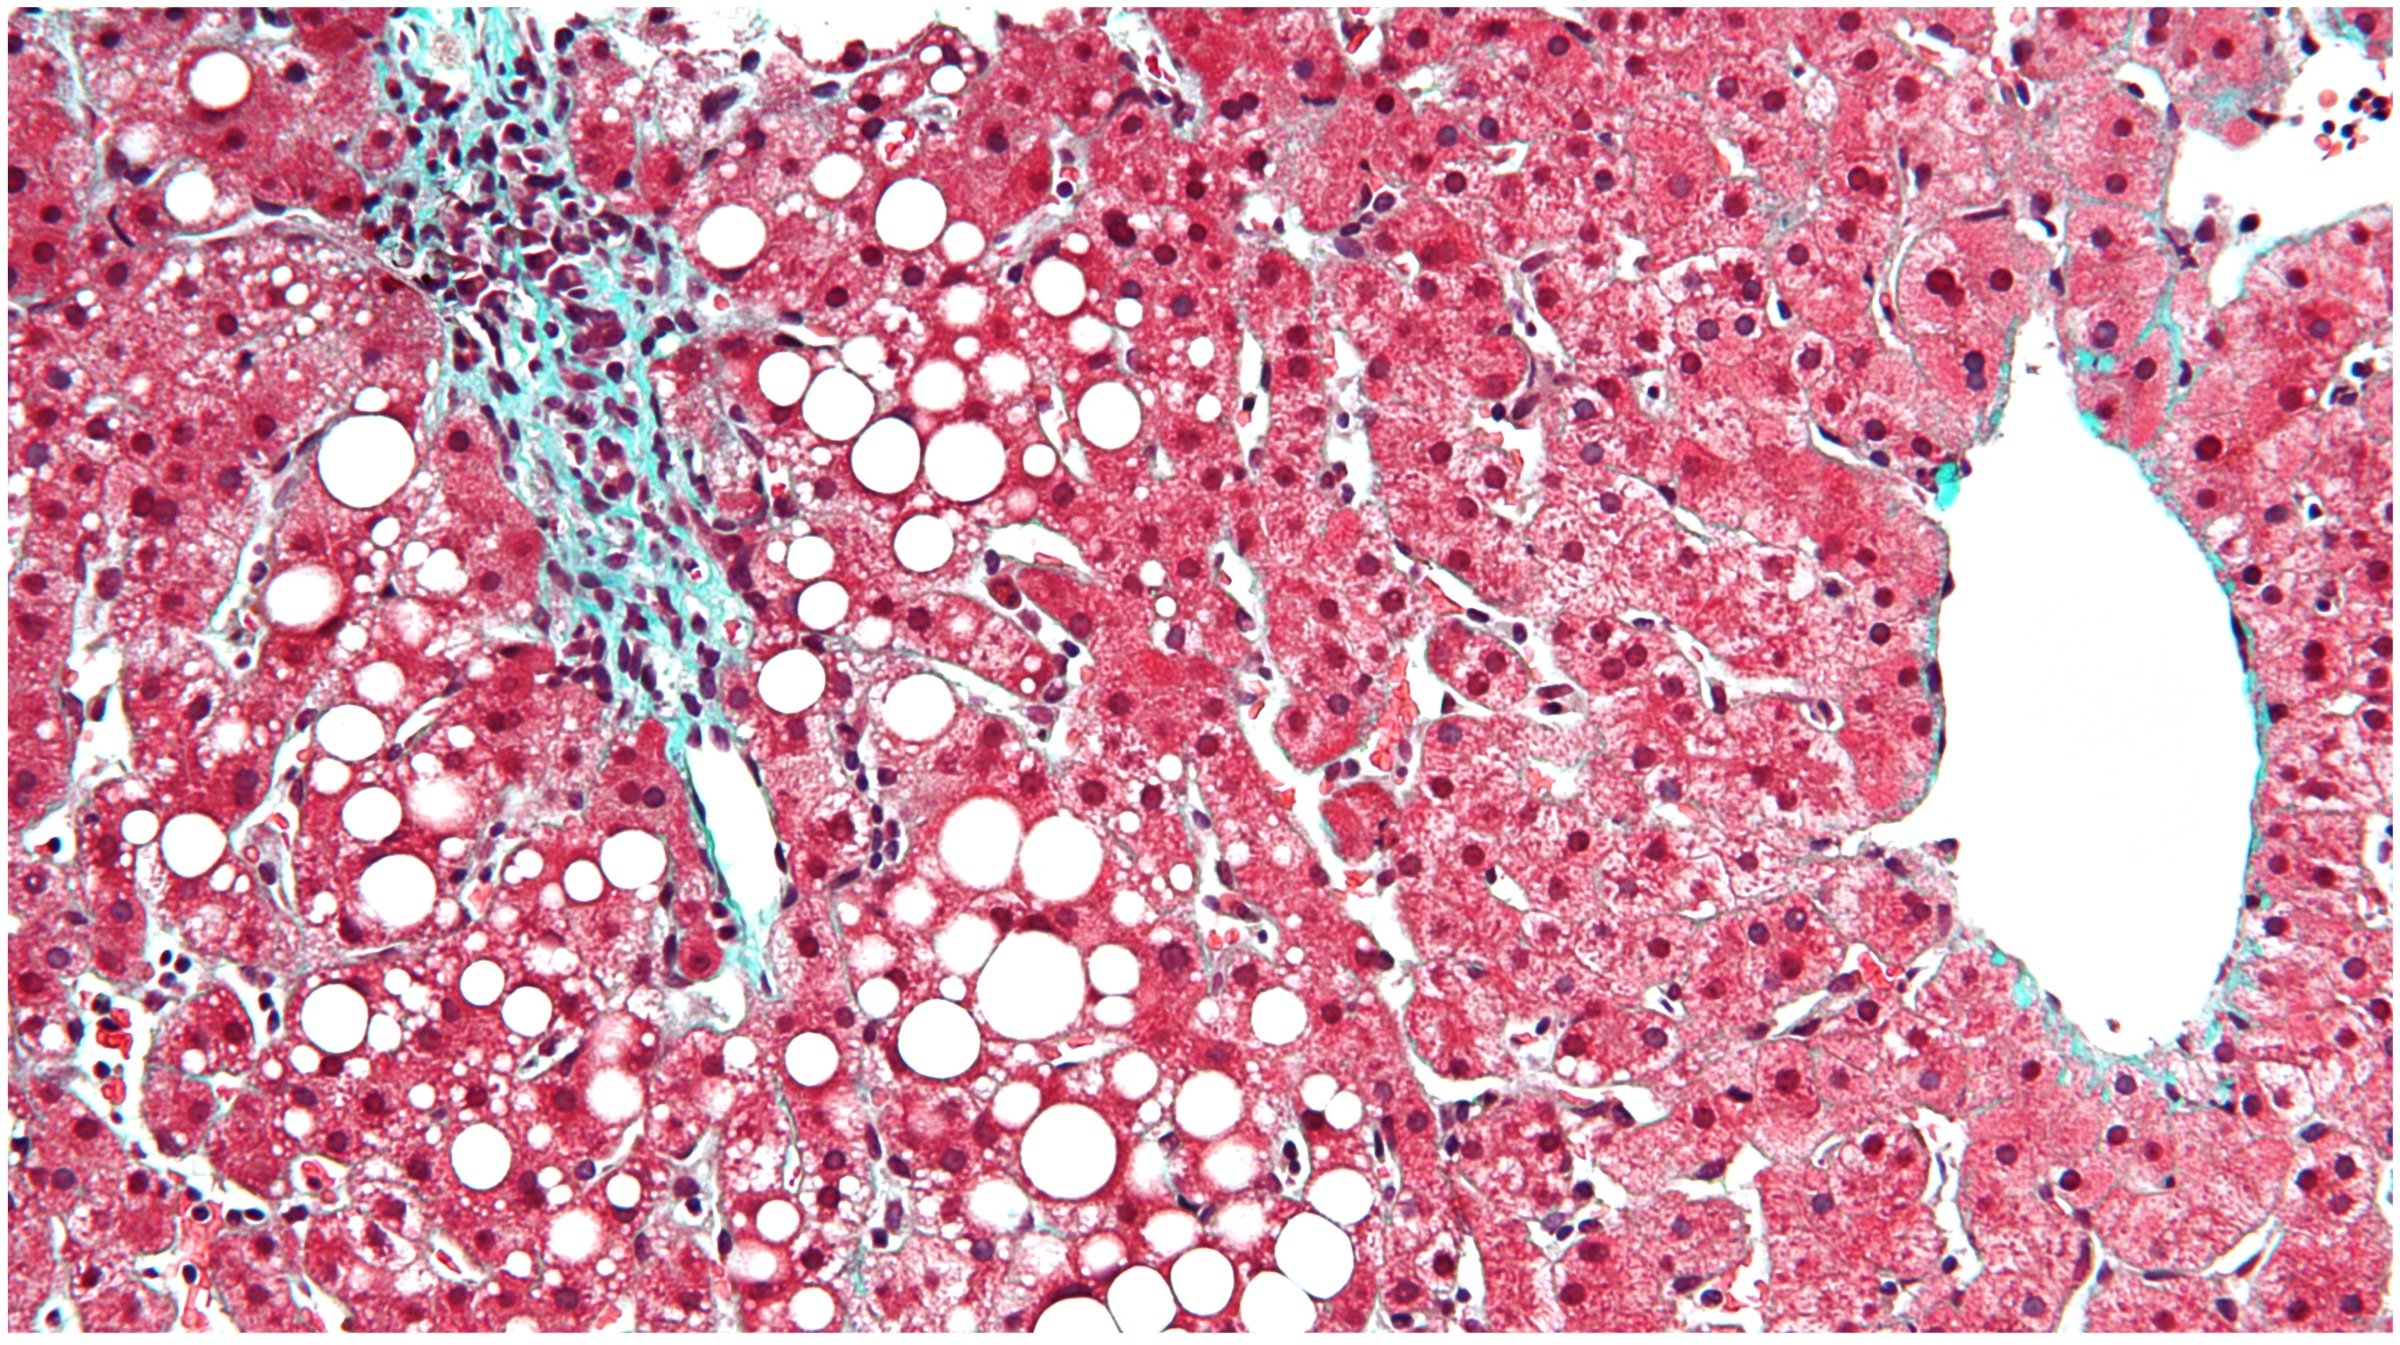

Familial hypobetalipoproteinemia (FHBL) is a disorder that deprives the body of the ability to absorb and transport fats. The protein truncating genomes in the APOB are the major causes of the disorder. The people with FHBL are usually at a high risk of developing fatty liver disease. Using genetics, the researchers can target the gene responsible for the same and thereafter greatly reduce the risk of coronary heart disease.